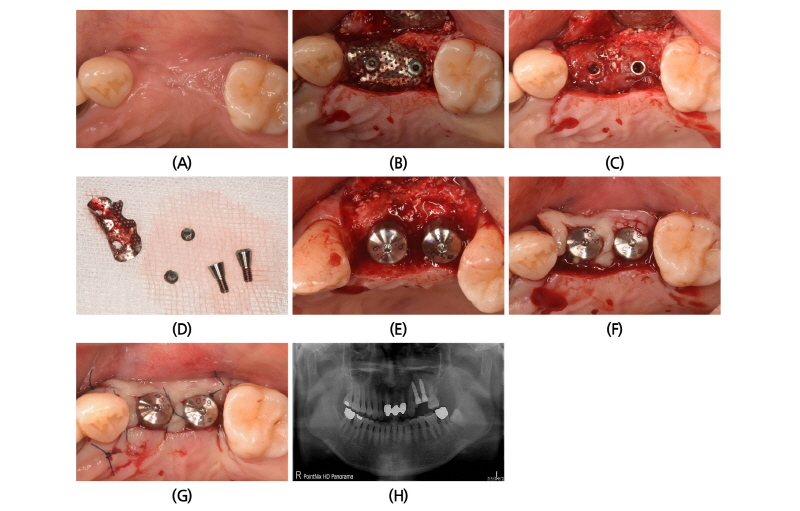

발치 후 7주후 임플란트 식립을 위하여 환자가 재내원하였다. 재촬영한 파노라마 상에서 #26부위의 상악동의 함기화가 빠르게 진행되어 상악동 거상술과 골이식술이 필요하게 되었다. 예상과 달리 임플란트 식립을 위한 판막 형성 후 #24, 25 부위에 임플란트 식립이 불가능할 정도의 좁은 치조제가 관찰 되었으며 #26부위도 빠르게 치조제의 흡수가 관찰되었다(Fig. 5B-5D).

임플란트 식립을 위한 드릴링 전에 협설 측으로 어느 정도 치조제 폭을 만들기 위하여 수평적인 골삭제를 실시하였다(Fig. 5E). 그 후에 #24부위는 치조제 위축이 심하여 드릴링 시 협측으로 드릴이 빠져나오게 되는데, 이때 핸드피스를 잡은 손을 구개측으로 밀면서 드릴링과 식립을 하여 25 Ncm의 초기고정을 얻었다. #25부위는 치조제의 중간 부분을 약간 벌리면서 식립을 하였고 #26부위는 ㈜네오바이오텍 SCA kit를 사용하여 상악동의 치조제 접근을 이용하여 상악동을 거상하고 별도의 골이식 없이 약 2.5 mm의 상악동 점막을 거상하고 상악동 하연의 피질골을 이용하여 2중 피질골 고정을 얻었다(Fig. 5F).

그 후에 #24, 25부위는 높이 1 mm의 스페이서(Spacer)를 연결하고, 노출된 나사선 부위는 자가골을 한층 덮고, 외부에는 탈단백우골을 이식하였다. 협설 측으로 임플란트 직경에 2 mm 이상의 충분한 협설측으로 골이식 후에 80도 이하로 구부린 무치악용 titanium mesh (E2)를 적용하였다. Titanium mesh는 GBR전용 덮개나사로 고정 상부에 2부분 고정하였고 GBR system에 있는 고정나사(fixing screw)로 #24,25 사이의 근단부에 고정을 추가하였다. 후에 이전의 증례에서 했던 것과 같은 방법으로 Colla-tape을 적용하였다. 봉합은 수평누상 봉합과 단속봉합을 2중으로 사용하였다. 봉합사는 4-0 나일론사를 사용하였으며 2주 후에 제거하였다. 2주 후에 일차유합을 잘 이루고 있었으며 4개월까지 일차유합을 유지하였다(Fig. 5G-5J).

4개월 후에 Uncovering을 위한 2차 수술 시 titanium mesh와 고정나사는 쉽게 제거가 되었으며 #24, 25 부위에 많은 골양 조직이 만들어진 것을 확인할 수 있다(Fig. 6A-6D).적절한 크기와 높이의 치유 지대주를 연결한 후에 단속봉합을 실시하였다(Fig. 6E, 6F). 충분한 치유가 일어날 수 있도록 약 4주간 기다린 후에 transfer type impression coping을 연결하고 인상 채득하였다(Fig. 6G). 보철물은 기성 지대주를 이용하였고 금속-도재관으로 보철물을 제작하여 영구접착하였다(Fig. 6H-6J).